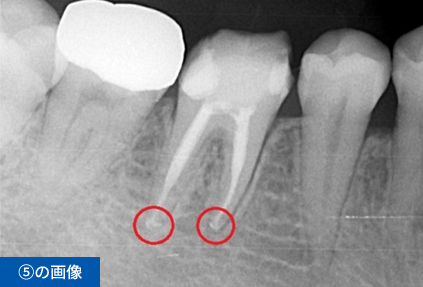

右下6番目の歯が、冷たいものがしみて痛いという主訴でご来院されました。